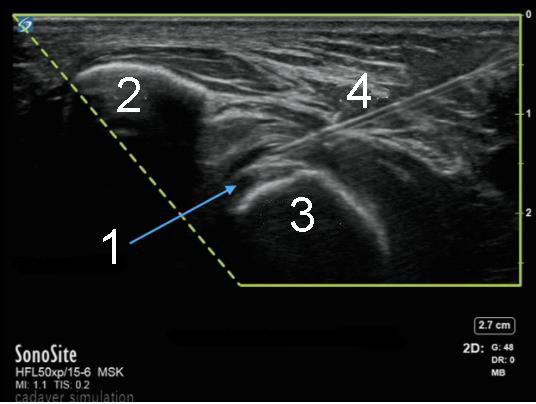

Elbow Distal Biceps Tendon Injection Image

Biceps Tendon

Ulna

Radial Tuberosity

Needle